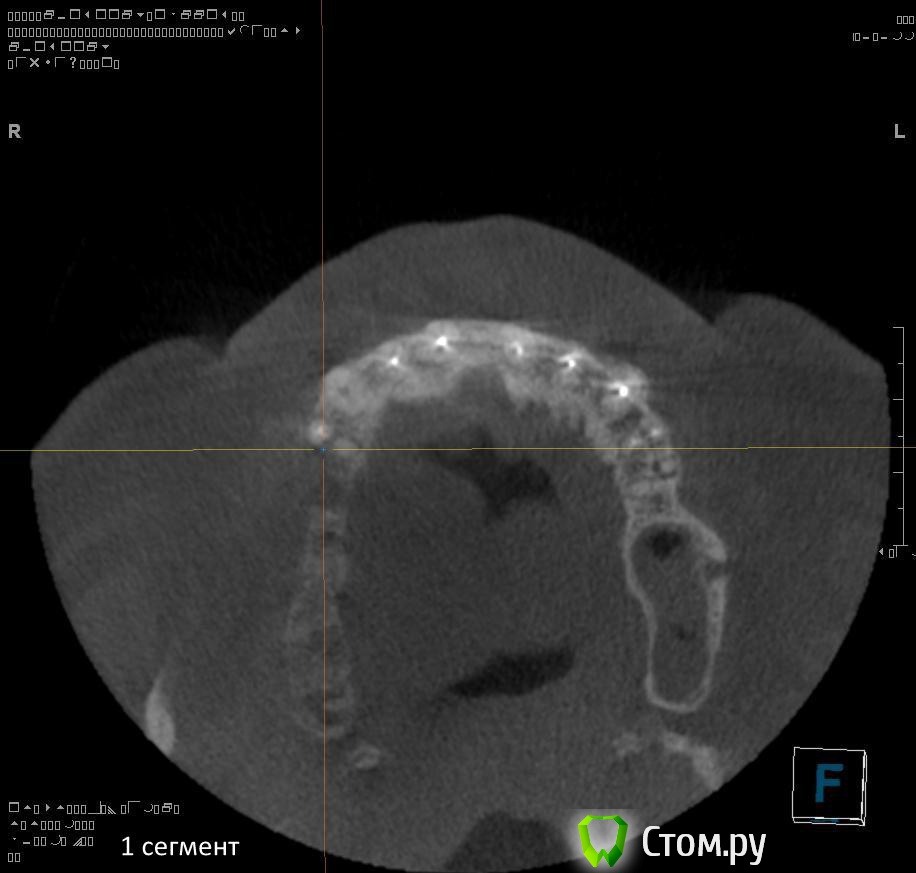

Провели обследование. Ортопед планирует оставить вверху 6 фронтальных зубов (возможно резцы пойдут на удаление), внизу только клыки. Далее последует удаление несостоятельных зубов + иммедиат протезы, продолжение реабилитации.

9. через 3 месяца после удаления 1.2, 1.1, 2.1, 2.2, 3.2, 3.1, 4.1, 4.2 зубов провести установку имплантатов во фронтальном отделе нижней, возможно верхней челюстей в позиции 1.2, 2.2 + 3.2, 4.2?

п.с. ДА, С ГИГИЕНОЙ ПОКА ЗАСАДА!!!)